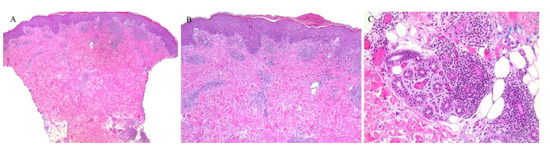

Although the inflammatory infiltrate of PL is commonly observed around the blood vessels, adnexotropic variants of PL have been described (Figure 7 and Figure 8). In one retrospective review, adnexotropism was observed in 97% of the specimens studied. It was also found that a denser periadnexal inflammation was observed in PLEVA/PLC overlap cases. This pattern of adnexotropism prompted the authors to suggest the descriptive term of a “T-shaped” inflammatory cell infiltrate, rather than a wedge-shaped infiltrate [37]. Syringotropic lymphocytes has been reported in one case of acral pityriasis lichenoides [38].

Figure 7. (AC) Pityriasis lichenoides et varioliformis acuta with perieccrine inflammation.

Figure 8. (AC) Pityriasis lichenoides chronica with perieccrine involvement.